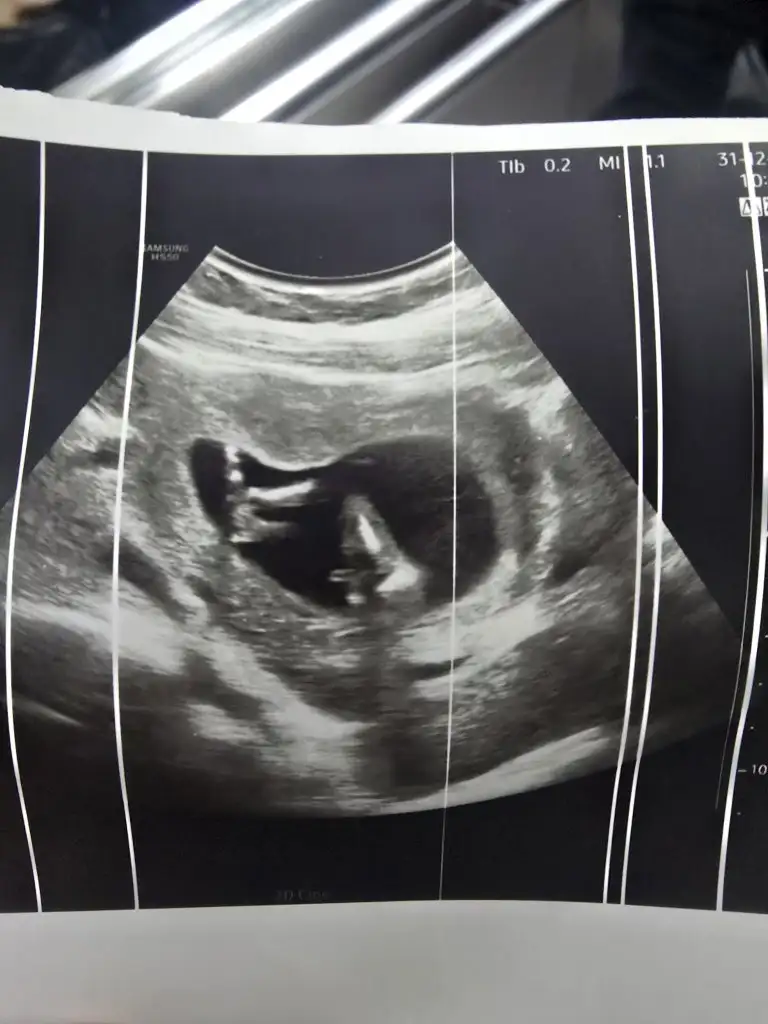

Hayırlısı artık yapacak bişe yokBanada başta bir çıkıntı var dediler kızda olablr iki hafta sonra gttgmzde erkek dediler

Ya bana da bakarmısınızErkek olablir benimkisine benziyor![]()

Keşke gerçek çıksaYa bana da bakarmısınızçok merak ediyorum da doktor erkek olabilir ama daha erken dedi Bidaha ki kontrolde tam belli olur dedi Eki Görüntüle 3528348 Eki Görüntüle 3528349

HahahahKeşke gerçek çıksasanada erkek diyeyim ayını ultrasondaki bebeğim gibi duruşu

Merve hanım şimdi çıktım özelden, ne diyosunuz ?Sağlıklı olsunlar da gerisi önemli değil![]()

14+4Kaç haftalık

Normalde kesin net cinsiyeti söylerler bu haftalardaBunun için yazdım

Söylediler sizin tahmininz hala geçerli mi o yüzden sordumNormalde kesin net cinsiyeti söylerler bu haftalarda